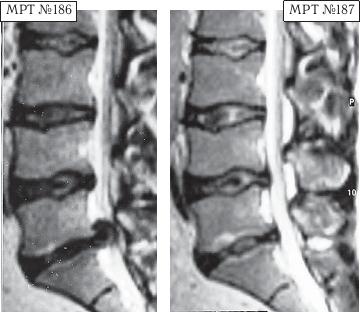

Следующий случай примечателен тем, что на МРТ-снимке можно наблюдать хорошо сохранившийся позвоночник профессионального спортсмена.

На МРТ № 186 наблюдается состояние поясничного отдела позвоночника: грыжи Шморля в сегментах LII-LIII, LIII-LIV, LIV-LV, спондилёз, секвестрированная грыжа межпозвонкового диска в сегменте LV-SI, жировая дегенерация в телах смежных позвонков данного сегмента, стеноз спинномозгового канала.

На МРТ № 187 — состояние поясничного отдела позвоночника после лечения методом вертеброревитологии.